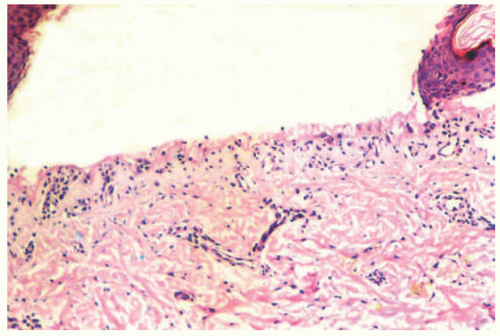

JEB is caused by splitting of the skin at the layer of the lamida lucida, reflected by histologic sections demonstrating a subepidermal blister (Figure 4-8).9 In contrast to EBS lesions, JEB lesions do not show cells or debris within the blister cavity (the so-called cell-free blister is characteristic).9 There is typically no significant associated inflammatory infiltrate.9 Absent or hypoplastic hemidesmosomes can be seen on ultrastructural examination, especially in more severe variants of the disease. IHC or DIF immunomapping identify BP antigen-1 on the roof of the blister, whereas laminin and type IV collagen are identified along the floor.

JEB is a group of inherited blistering disorders characterized by blister formation in the lamina lucida of the dermal epidermal junction. Severe forms are lethal in infancy. Histologic sections show a subepidermal blistering without cells in the blister cavity. BP antigen-1 is generally identified on the roof of the blister, whereas laminin and type IV collagen are most often found on the floor of the blister.